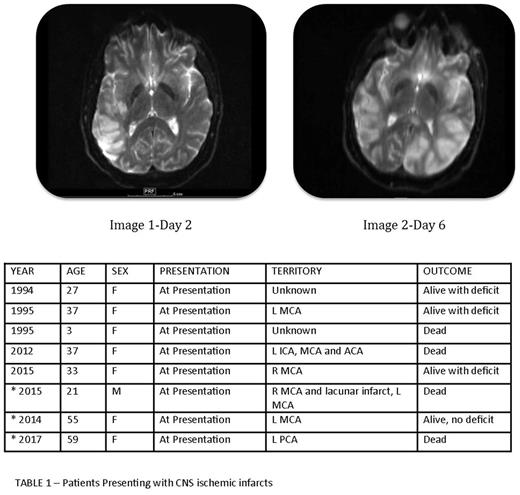

On review of the literature, five cases were described where patients with newly diagnosed APL presented with CNS arterial thrombosis; 3 patients are alive with neurologic deficit and 2 are dead. (Table 1).

Patient 1- 21-year-old male who presented to an outlying hospital with expressive aphasia. MRI scan showed large right temporoparietal infarction. Labs showed WBC 21.6, platelets 9,000, low fibrinogen, elevated PT and elevated d-dimer. High-risk APL was confirmed and ATRA and IV dexamethasone were started. Heparin drip was initiated to decrease risk of further ischemic insult. Worsening neurologic symptoms 4 days later led to a repeat MRI scan, which showed progressive right sided infarct and a new infarct in the left distal territory of the middle cerebral territory and expired shortly thereafter. Images 1 and 2 show infarcts on day 2 and 6 of admission.